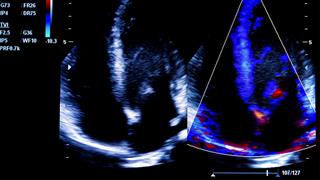

Η καρδιακή ανεπάρκεια ως επιπλοκή της λοίμωξης COVID-19

H καρδιακή ανεπάρκεια ως επιπλοκή της λοίμωξης COVID-19 δεν είναι ιδιαίτερα συχνήσε ασθενείς χωρίς προηγούμενη διάγνωση καρδιακής ανεπάρκειας αλλά όταν συμβαίνει συνδέεται με σοβαρές ενδονοσοκομειακές επιπλοκές.

COVID-19 και καρδιακές αρρυθμίες

'Eχουν περιγραφεί υπερκοιλιακές ταχυκαρδίες, κολπική μαρμαρυγή, κολπικός πτερυγισμός, πλήρης κολποκοιλιακός αποκλεισμός, καρδιακή ανακοπή, πολύμορφη και μονόμορφη κοιλιακή ταχυκαρδία.